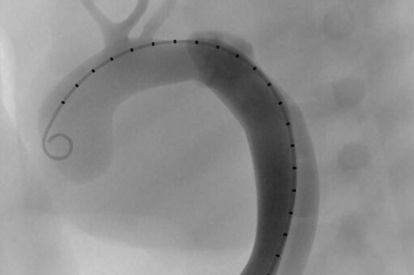

EVAR (Endovascular Aneurysm Repair) Module

TEVAR Module

Advanced TEVAR Module